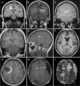

Tumefactive multiple sclerosis

Tumefactive multiple sclerosis is a condition in which the central nervous system of a person has multiple demyelinating lesions with atypical characteristics for those of standard multiple sclerosis (MS). It is called tumefactive as the lesions are "tumor-like" and they mimic tumors clinically, radiologically and sometimes pathologically.These atypical lesion characteristics include a large intracranial lesion of size greater than 2.0 cm with a mass effect, edema and an open ring enhancement. [Source: Wikipedia ]